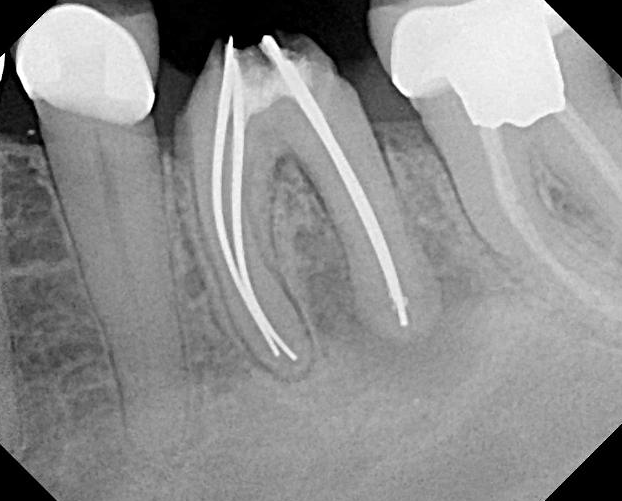

Silver Points In Endodontics Uses . silver points were historically indicated and well accepted as a root canal obturation material; silver cones are no longer utilised for root canal obturation [ 9, 10 ]. clinicians frequently encounter endodontically treated teeth that contain silver points within their roots. silver cones (also referred to as silver points) are a historic obturation material that is. Sargenti and richter proposed the principle of. silver points were historically indicated and well accepted as a root canal obturation material;. radiographs show that silver points can be used satisfactorily in teeth that are to receive posts and root canal fillings may. apart from gp the alternate materials which have been tried are plastics (resilon), solids or metal cores (silver.

silver points were historically indicated and well accepted as a root canal obturation material; radiographs show that silver points can be used satisfactorily in teeth that are to receive posts and root canal fillings may. silver points were historically indicated and well accepted as a root canal obturation material;. clinicians frequently encounter endodontically treated teeth that contain silver points within their roots. apart from gp the alternate materials which have been tried are plastics (resilon), solids or metal cores (silver. Sargenti and richter proposed the principle of. silver cones are no longer utilised for root canal obturation [ 9, 10 ]. silver cones (also referred to as silver points) are a historic obturation material that is.

Case Report of a Silver Point Removal TriCity DevTriCity Dev Silver Points In Endodontics Uses radiographs show that silver points can be used satisfactorily in teeth that are to receive posts and root canal fillings may. silver points were historically indicated and well accepted as a root canal obturation material; silver cones are no longer utilised for root canal obturation [ 9, 10 ]. silver cones (also referred to as silver. Silver Points In Endodontics Uses.

Molar retreatment with silver point removal Norfolk Endodontics Silver Points In Endodontics Uses Sargenti and richter proposed the principle of. silver cones (also referred to as silver points) are a historic obturation material that is. silver cones are no longer utilised for root canal obturation [ 9, 10 ]. clinicians frequently encounter endodontically treated teeth that contain silver points within their roots. silver points were historically indicated and well. Silver Points In Endodontics Uses.